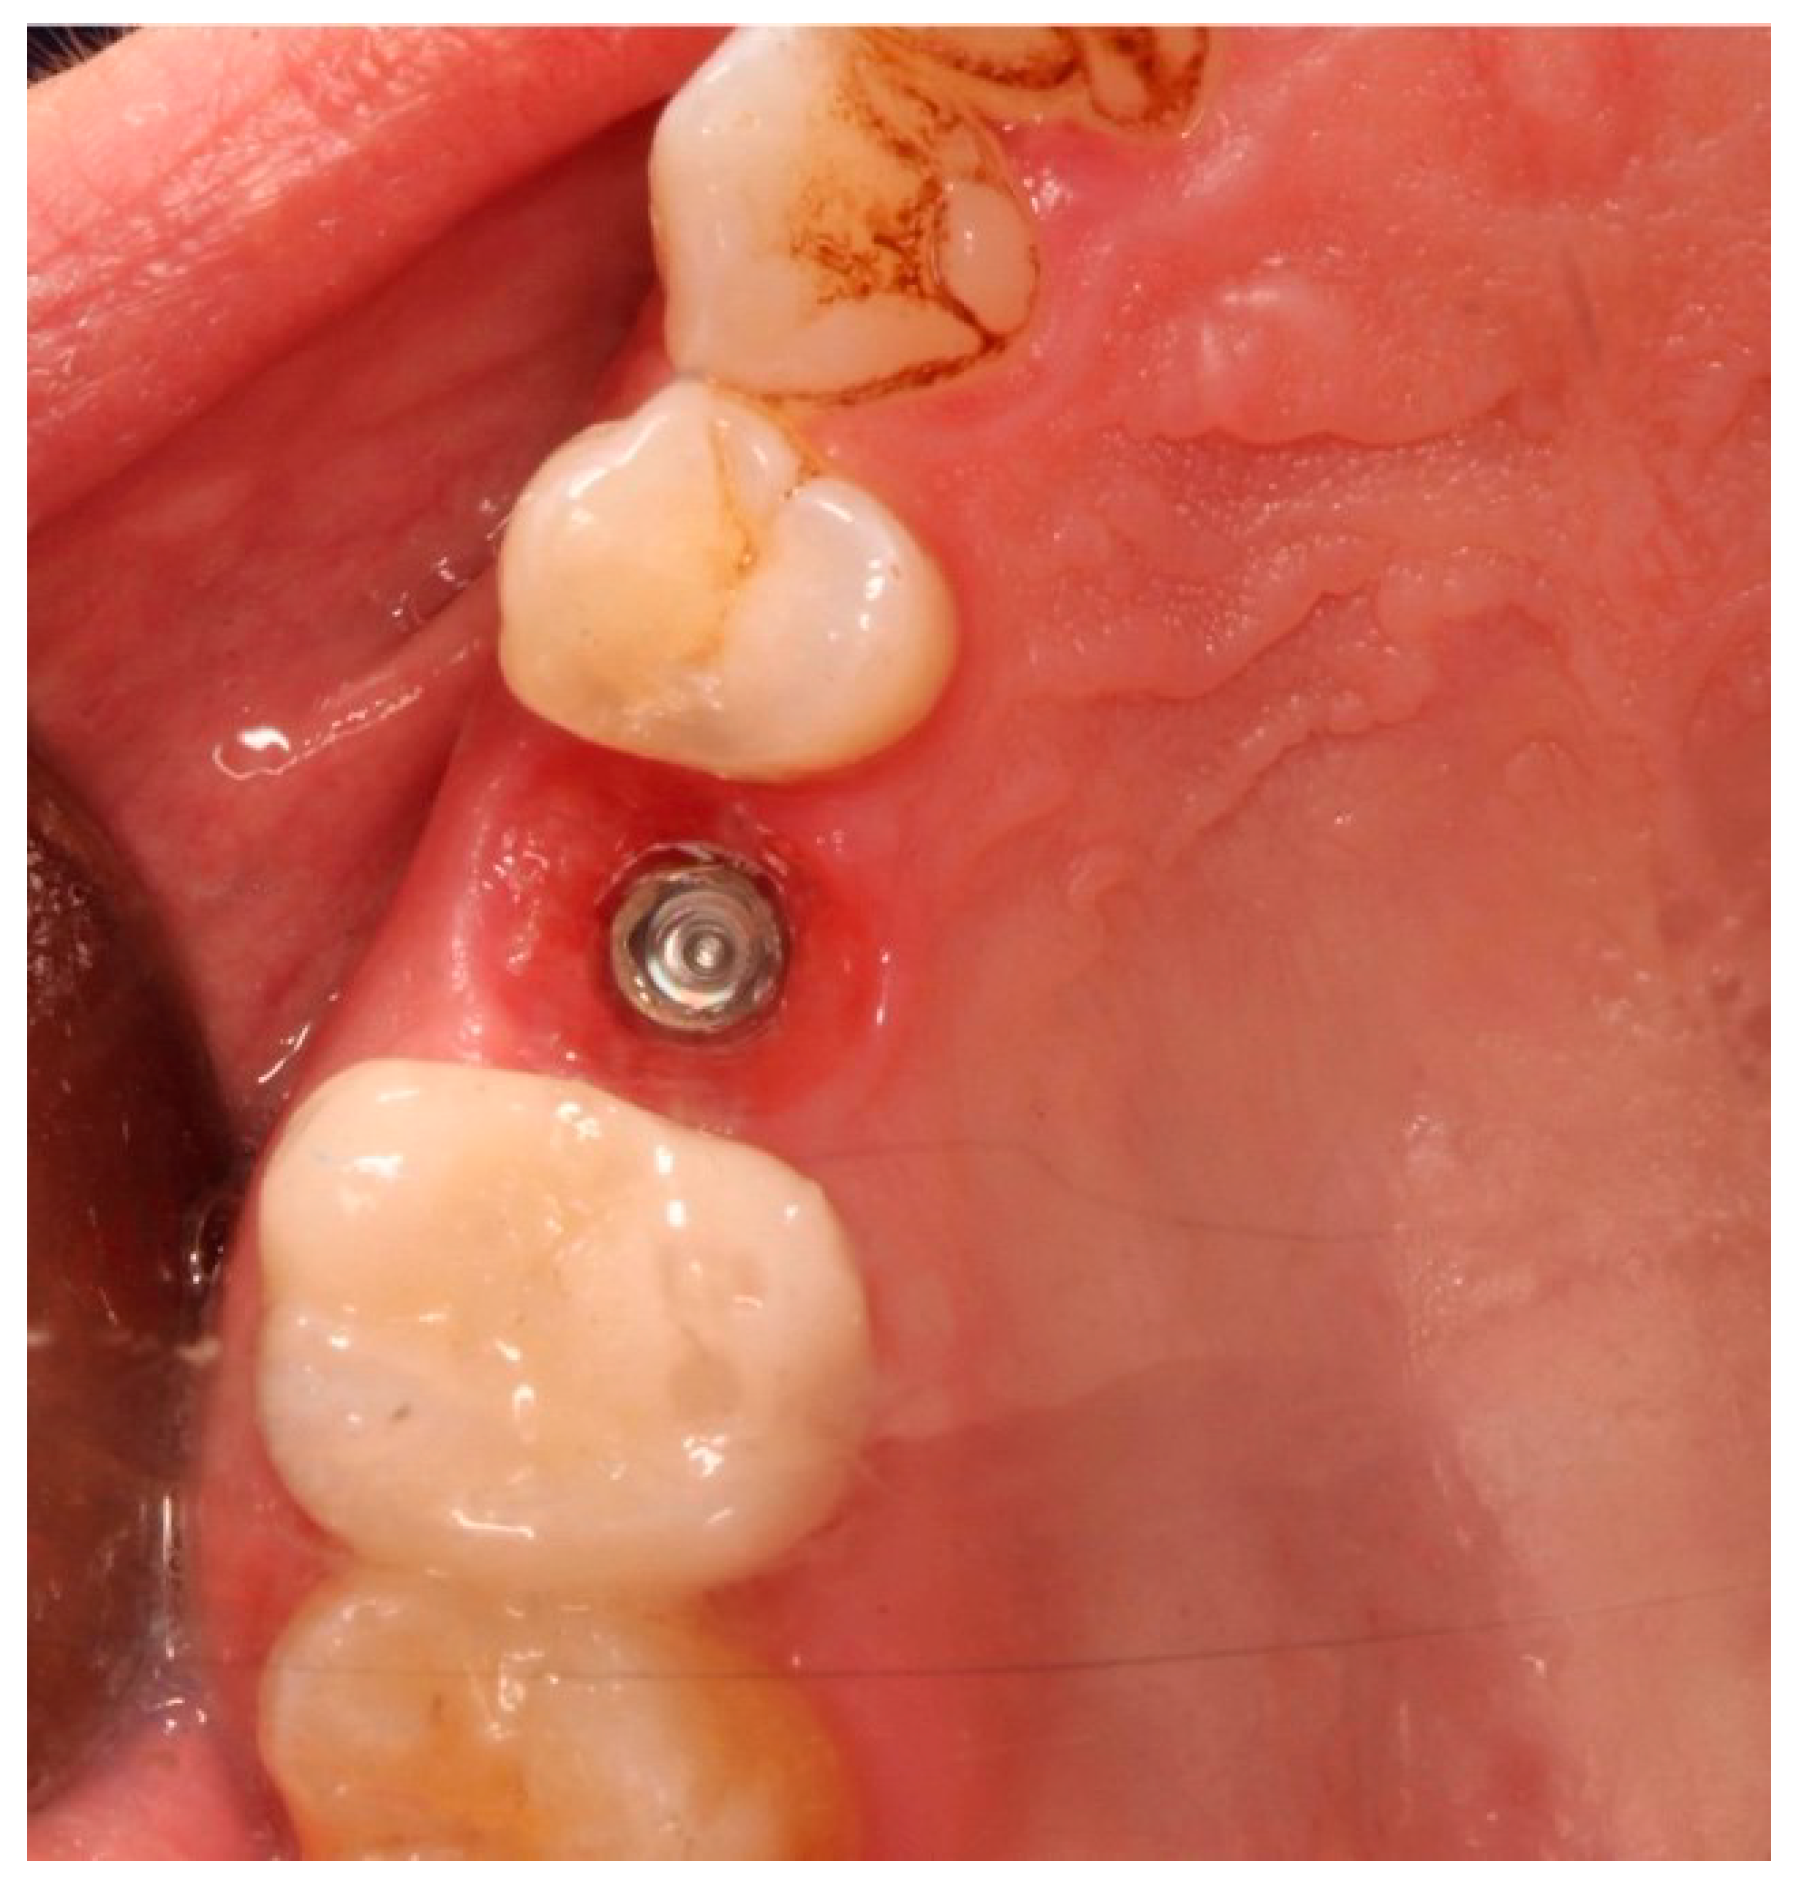

Figure 6.

Healing abutment in situ after implant insertion.

This attention to detail ensured precise fit and optimal soft tissue healing around the abutment.